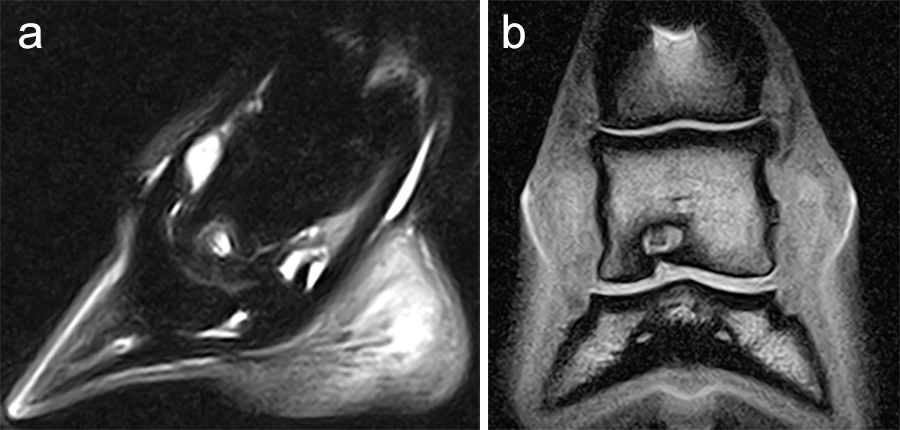

A subchondral middle phalanx bone cyst was identified on a clinically sound 3-year-old Warmblood Gelding during radiographic screening. The osseous lesion was located at the medial and distal aspect of the middle phalanx on the left front limb. Radiographs indicated mild sclerosis of the trabecular bone surrounding the cyst. A magnetic resonance imaging examination confirmed discrete communication with the distal interphalangeal joint (Fig 6). The treatment of choice was surgery, which included placing a cortical lag screw or compression screw across the subchondral bone cyst. This technique aims to promote new bone formation by altering the biomechanical bone environment. A 4.5 mm headless compression screw was placed across the cyst with the veterinary screw targeting clamp.